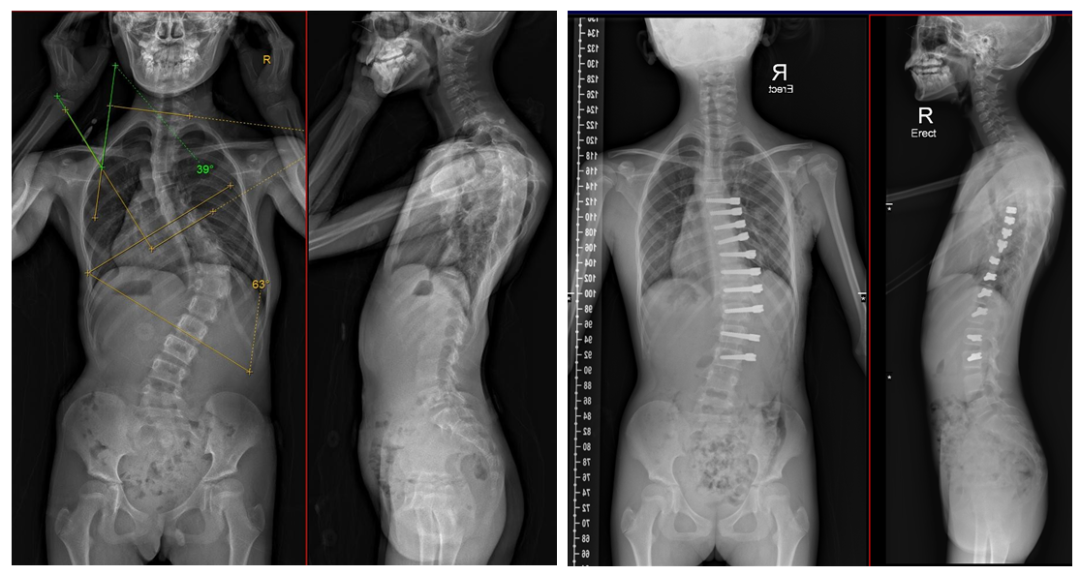

左图为术前全脊柱正侧位X线片,主弯Cobb角63°。右图为术后全脊柱正侧位X线片,侧弯角度明显减小,且随着生长发育,侧弯会进一步改善。